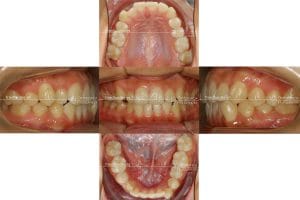

Fotos de antes del tratamiento

Después de 20 meses y un refinamiento se consiguió clase I en ambos lados y centrar la línea media inferior con la superior.

Podemos ver que el final del tratamiento en boca coincide perfectamente con la planificación del Clincheck final